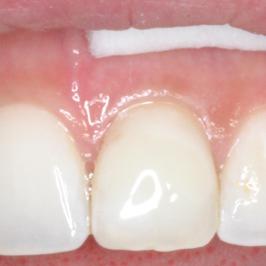

Au bout de 2 mois et 4 séances de blanchiment interne

Discoloration due à un traitement de racine

Après 1 mois et 2 séances de blanchiment interne